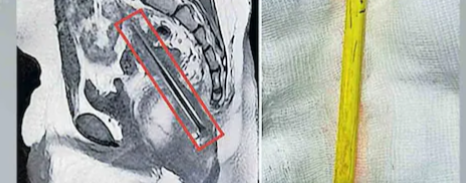

เดเดพเตฝเดฎเตเดเตเดเต เดตเตเดฆเดจเดฏเตเดฎเดพเดฏเดฟ เดเดถเตเดชเดคเตเดฐเดฟเดฏเดฟเดฒเตเดคเตเดคเดฟ; เดเดฟเดเดฟเดคเตเดธเดฏเตเดเตเดเดฟเดเต โเดเตเดตเดฟเดธเตเดฑเตเดฑเตโ: โเดเดพเดฃเดพเดคเดพเดฏโ เดชเตเตปเดธเดฟเตฝ เดถเดธเตเดคเตเดฐเดเตเดฐเดฟเดฏเดฏเดฟเดฒเตเดเต เดชเตเดฑเดคเตเดคเตเดเตเดคเตเดคเต

เดเตเดเตเดเดฟ โ เดเดพเดจเดกเดฏเดฟเดฒเต เดเตเดฒเดพเดธเต เดฎเตเดฑเดฟเดฏเดฟเตฝ โเดเดพเดฃเดพเดคเดพเดฏโ เดชเตเตปเดธเดฟเดฒเดฟเดจเตเดฑเต 12 เดธเตเดจเตเดฑเดฟเดฎเตเดฑเตเดฑเตผ เดจเตเดณเดฎเตเดณเตเดณ เดญเดพเดเด เดเดเตเดเต เดตเดฏเดธเตเดธเตเดเดพเดฐเดจเตเดฑเต เดเดเตเดชเตเดชเดฟเดจเตเดฑเต เดชเดฟเตปเดญเดพเดเดคเตเดคเต เดจเดฟเดจเตเดจเต เดเตเดเตเดเดฟเดฏเดฟเดฒเต เดเดถเตเดชเดคเตเดฐเดฟเดฏเดฟเตฝ เดถเดธเตเดคเตเดฐเดเตเดฐเดฟเดฏเดฏเดฟเดฒเตเดเต เดชเตเดฑเดคเตเดคเตเดเตเดคเตเดคเต. เดเดพเตฝเดฎเตเดเตเดเต เดตเตเดฆเดจเดฏเตเดฎเดพเดฏเดฟ เดเดถเตเดชเดคเตเดฐเดฟเดฏเดฟเดฒเตเดคเตเดคเดฟเดฏ เดเตเดเตเดเดฟเดฏเตเดเต เดเดฟเดเดฟเดคเตเดธเดฏเตเดเตเดเดฟเดเตเดฏเดพเดฃเต เดเดฐเตเดฏเตเด เด เดฆเตเดญเตเดคเดชเตเดชเตเดเตเดคเตเดคเตเดจเตเดจ โเดเตเดตเดฟเดธเตเดฑเตเดฑเตโ. เดเดพเดจเดกเดฏเดฟเตฝ เดชเตเดฐเดตเดพเดธเดฟเดฏเดพเดฏ…